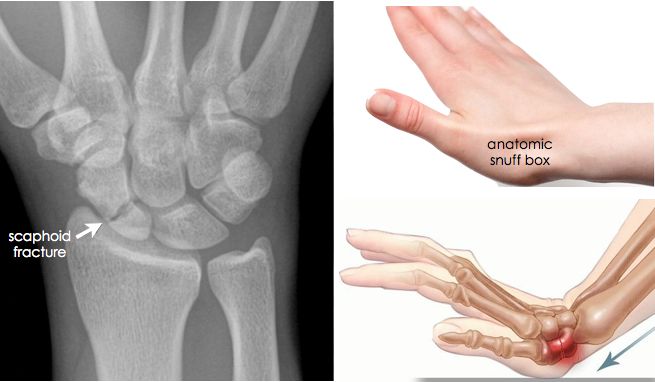

골치아픈 골절이 될 가능성 이 높은 ‘주상골 골절' 입니다. 엄지손가락 뼈와 연결되어 있는 '큰마름뼈' 안쪽에 있는 뼈 입니다.

이 배모양의 뼈가 이야기되는 이유는 생각보다 많은 환자분들이 골절인지 놓치기 쉽기도 하며, 불유합이 되기 쉬운 뼈이기 때문입니다. 손의 골절중에는 가장 흔한 골절로서, 진단이 늦어지면 치료도 늦어지게 됩니다. 즉, 진료를 받지 않는다면 예후가 나빠지는 경우가 많습니다. 따라서, 손목을 삐었는데 좀 심하게 삐엇다 싶으면 무조건 영상의학적 검사(X-ray)를 시행해 보아야 합니다. 특이한 점은 처음 시행한 엑스레이에서 '음성' 이 나왔더라도, 통증이 계속되거나 이 주상골 골절이 의심되는 경우에는 '2주 후'에 엑스레이를 다시 찍어볼 필요가 있습니다.

골절은 대게 Waist 라고 불리는 가운데 부분에서 진행되는 경우가 많으며(2), 10%는 근위부(1), 나머지 극소수(3)에서는 원위부에서 이러한 골절이 이러나게 됩니다.

진단은 Anatomical Snuff Box 라고 불리는 부위에 통증이 있으며 주상골을 눌러보았을 때 통증이 있는 경우 임상적으로 진단이 가능하며, 초기 방사선 사진에서는 골절이 보이지 않더라도 반드시 2주 뒤 2차 방사선 사진을 촬영하여야 합니다. MRI 에서 모호한 골절의 경우 2.8일이 경과한 후에 가돌리늄을 이용해 증강시켜 골절을 확인할 수 있습니다. (혈류량을 확인해 볼 수도 있습니다)